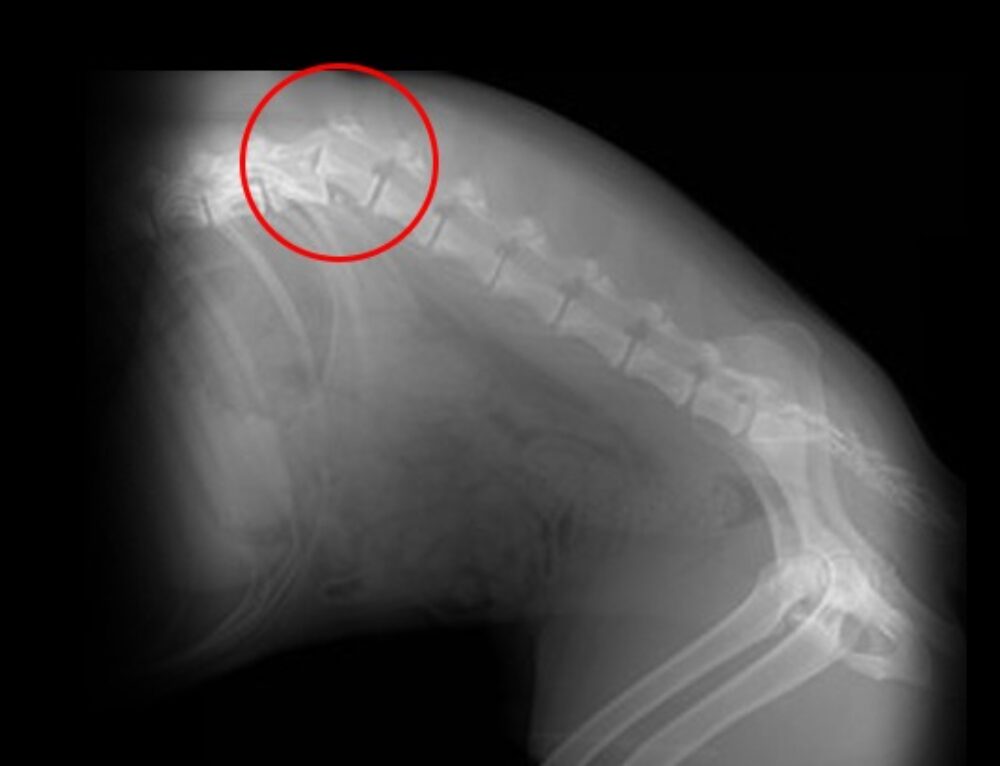

Feline hip dysplasia A challenge to recognise and treat Karen Perry